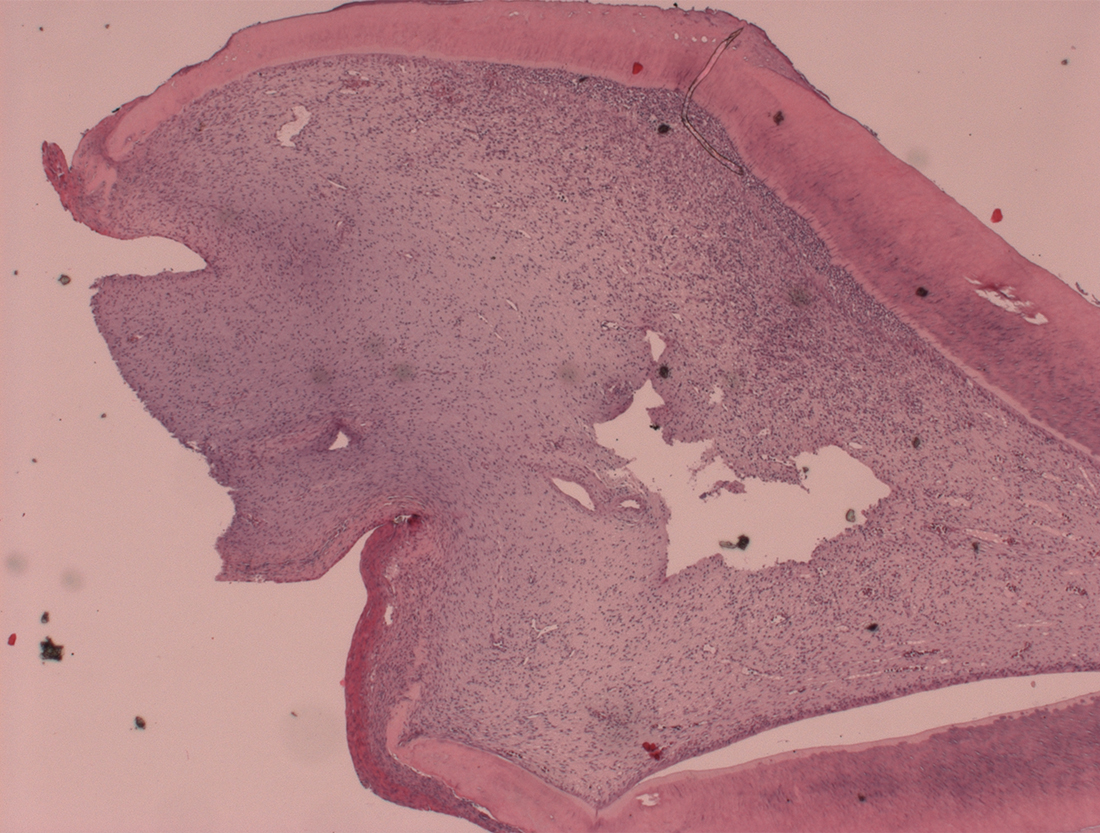

Home La gestione dei denti neonatali: nuove evidenze istologiche possono modificare l’approccio terapeutico figure-2

figure-2

figure-1

figura3